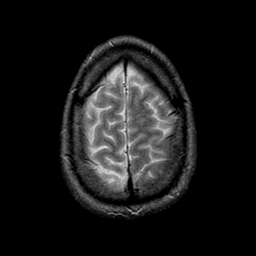

glioma overlay -- Slice #24

[Home][Help][Clinical] Slice 24